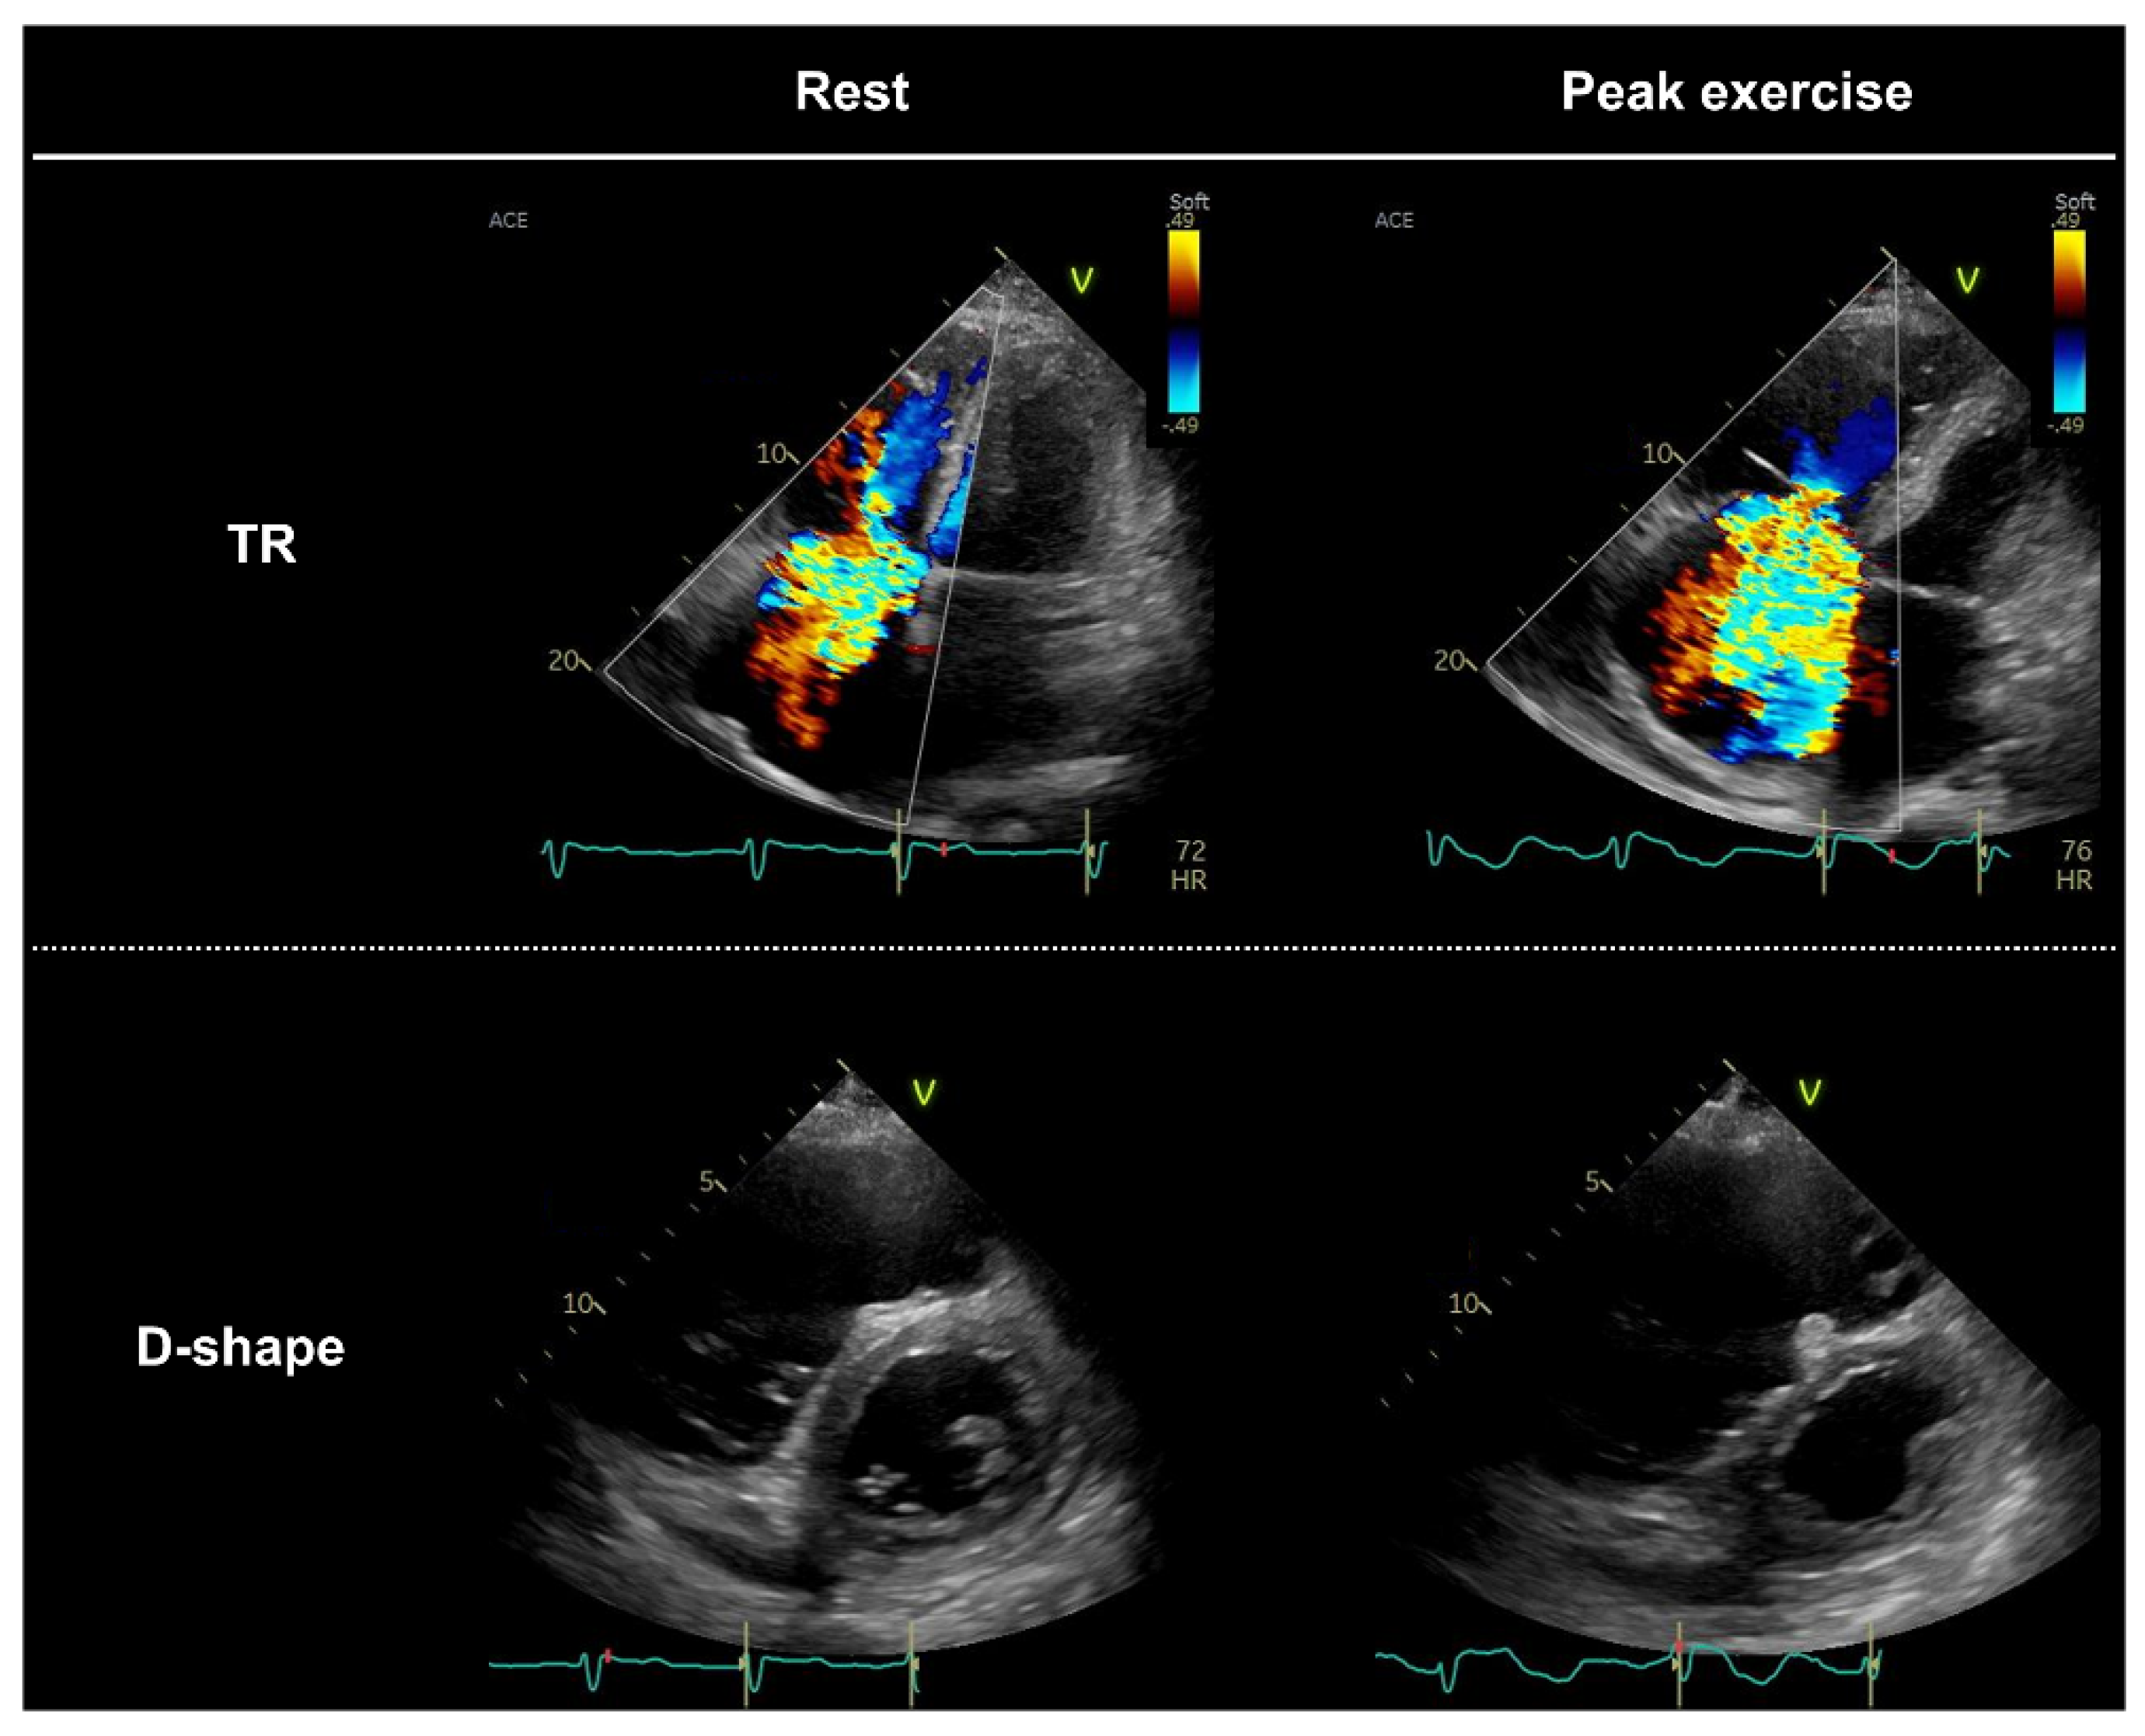

| Identification of pulmonary hypertension during exercise is useful for diagnosing HFpEF. Pulmonary hypertension may be underestimated in some patients, such as those with severe TR or those with very high RAP during exercise. How should this be addressed? | It is unclear how the underestimation of the TR gradient in patients with severe TR should be addressed. Further studies are required. Measurements of peripheral venous pressure may be a useful alternative to RAP measurements during exercise [56,58]. |